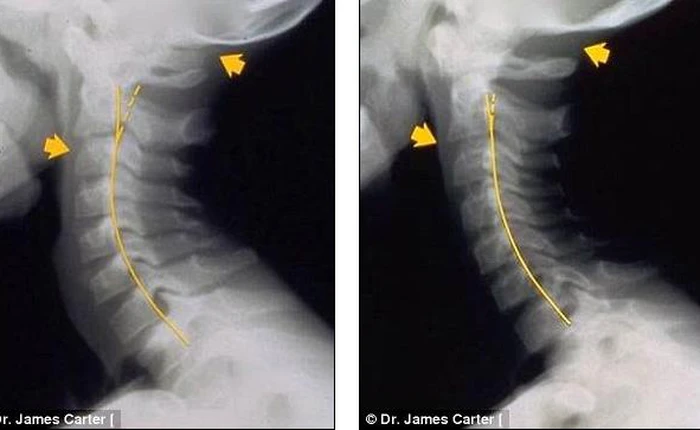

Những bức ảnh này có thể khiến những "con nghiện smartphone" phải giật mình.